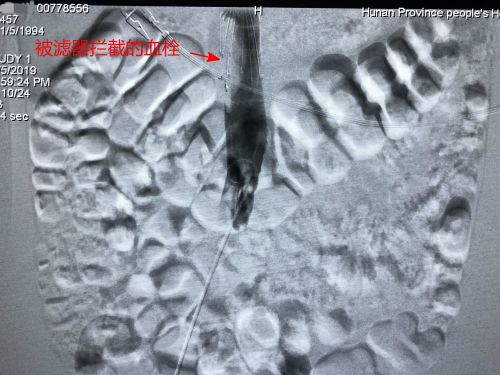

术前,下肢深静脉血栓形成。

通过手术,血栓被滤网拦截。